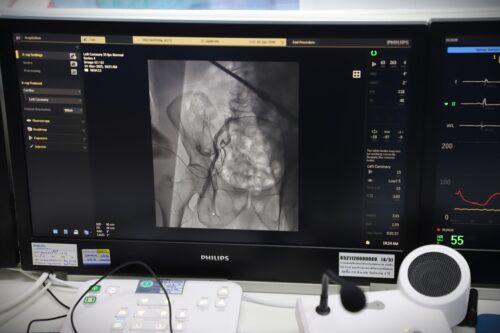

(วันที่ 2 ธค. 2568) ศูนย์หัวใจสิริกิติ์ ภาคตะวันออกเฉียงเหนือ ยกระดับการรักษาผู้ป่วยโรคลิ้นหัวใจเอออร์ติกตีบรุนแรง ด้วยหัตถการ TAVI (Transcatheter Aortic Valve Implantation) หรือการเปลี่ยนลิ้นหัวใจเอออร์ติกโดยไม่ต้องผ่าตัดเปิดหน้าอก ซึ่งเป็นเทคโนโลยีที่ช่วยลดความเสี่ยงและเพิ่มความปลอดภัย โดยเฉพาะในผู้ป่วยสูงอายุหรือผู้ที่ไม่เหมาะสมต่อการผ่าตัดใหญ่

รศ.นพ.ดนณ แก้วเกษ อายุรแพทย์หัวใจและหลอดเลือด กล่าวว่า โรคลิ้นหัวใจเอออร์ติกตีบขั้นรุนแรงเป็นภาวะที่พบได้มากในผู้สูงอายุ และอาจนำไปสู่อาการเหนื่อยง่าย เจ็บหน้าอก เวียนศีรษะ หรือภาวะหัวใจล้มเหลวได้ การรักษาแบบดั้งเดิมคือการผ่าตัดเปิดหน้าอกเพื่อเปลี่ยนลิ้นหัวใจ แต่ผู้ป่วยบางรายมีความเสี่ยงสูง ไม่เหมาะกับการผ่าตัด วิธี TAVI จึงเข้ามามีบทบาทสำคัญ ซึ่งข้อดีของ TAVI คือไม่ต้องเปิดหน้าอก ไม่ต้องหยุดหัวใจ โดยแพทย์จะผ่าตัดใส่ลิ้นหัวใจเทียมผ่านทาง หลอดเลือดแดงที่ขาหนีบ ทำให้ผู้ป่วยฟื้นตัวเร็วมาก หลายรายกลับบ้านได้ภายใน 2–3 วัน

ในส่วนของขั้นตอนการรักษา ศูนย์หัวใจสิริกิติ์ฯ ใช้เทคโนโลยีลิ้นหัวใจรุ่นใหม่ที่พัฒนาให้วางตำแหน่งได้แม่นยำ ลดความเสี่ยงของภาวะแทรกซ้อน เช่น เลือดออก หลอดเลือดบาดเจ็บ หรือการนำไปสู่ภาวะการเต้นผิดจังหวะ ทีมแพทย์ Heart Team ซึ่งประกอบด้วยแพทย์โรคหัวใจ แพทย์หัตถการ แพทย์ศัลยกรรมหัวใจ วิสัญญีแพทย์ และทีมพยาบาลเฉพาะทาง จะร่วมกันวางแผนการรักษาและประเมินอย่างละเอียดในผู้ป่วยแต่ละราย เพื่อให้ได้ผลลัพธ์ที่ปลอดภัยที่สุด